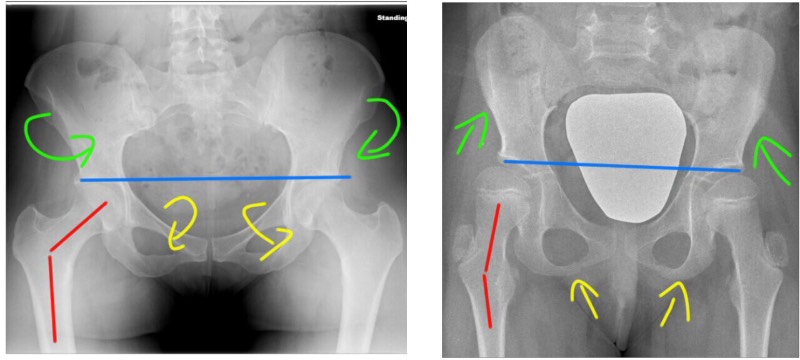

Анатомия и упражнения: Перекос таза и мышцы бедра